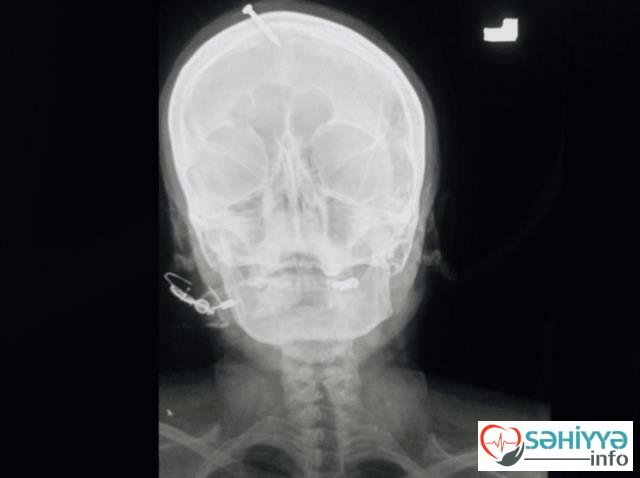

Sehiyye.info Metbuat.az-a istinadən xəbər verir ki, 3 qız anası olan qadın 4-cü dəfə hamilə qalandan sonra oğlan uşağı arzulayıb. İddialara görə, əri qadına deyib ki, 4-cü uşaq da qız olsa, o boşanacaq. Buna görə də, qadın 4-cü uşağın oğlan olması üçün yerli sakinlər arasında "şəfa verən" kimi tanınan saxta dindara müraciət edib. Saxta dindar qadını inandırıb ki, o baş nahiyyəsinə mismar vursa oğlan uşağı dünyaya gətirəcək.

Qadın buna inanıb və baş nahiyyəsinə mismar vurulmasına razılıq verib. Lakin saxtakar mismarı dərinə vurduğuna görə, qadın xəsarət alıb. O xəstəxanaya yerləşdirilib. Polis isə saxtakarı axtarır.